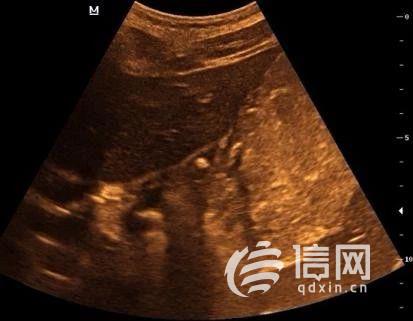

就在这时,有朋友给小英的妈妈推荐了胃肠超声检查。按照约定的时间,小英一大早就空腹来到齐鲁医院青岛院区健康管理中心,喝下了医生为她特制的“黑芝麻糊”后,B超室医生为她进行了胃肠超声检查,结果发现小英胃的贲门口位置有一个大约5mm的溃疡,与她疼痛的位置相符。

胃肠超声显示小英胃的贲门口位置有一个大约5mm的溃疡( 来源:信网)